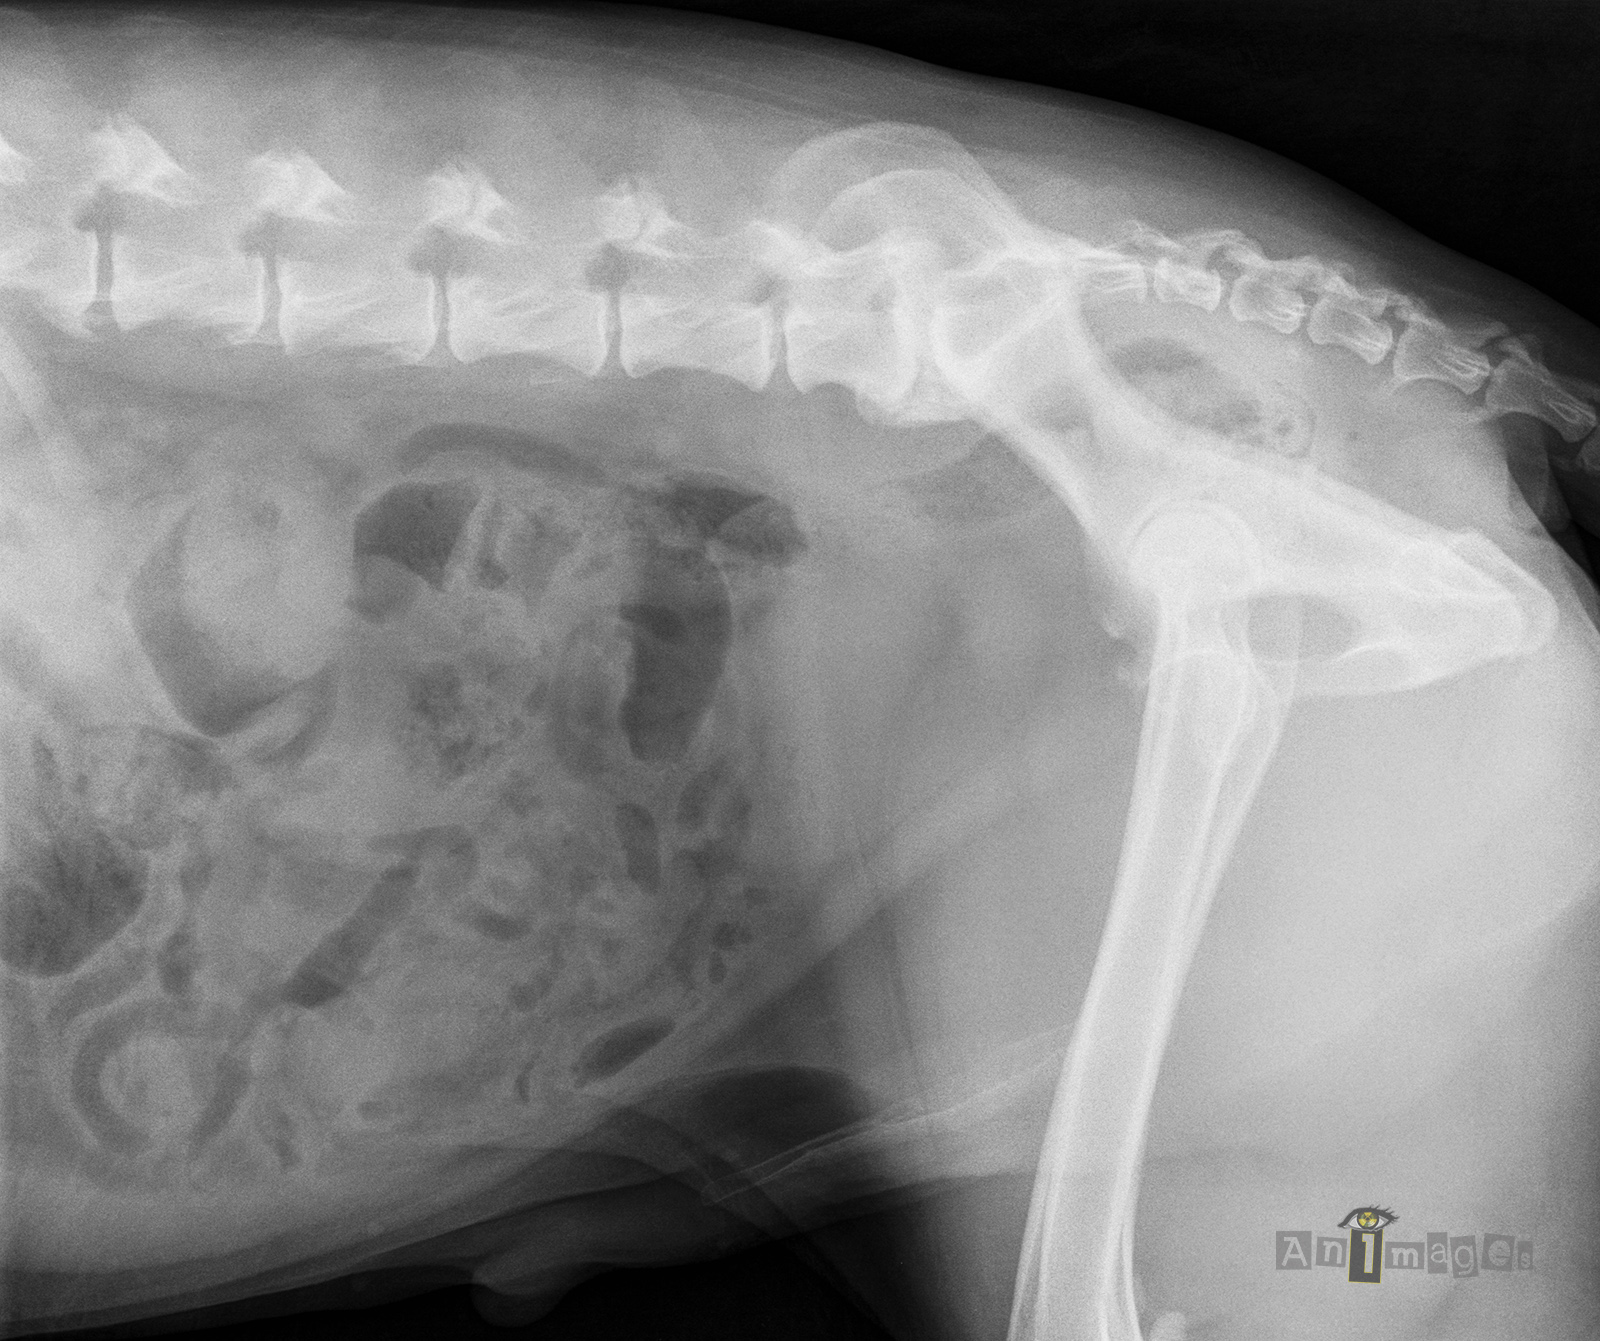

lat D caudale

Latérale droite – caudale